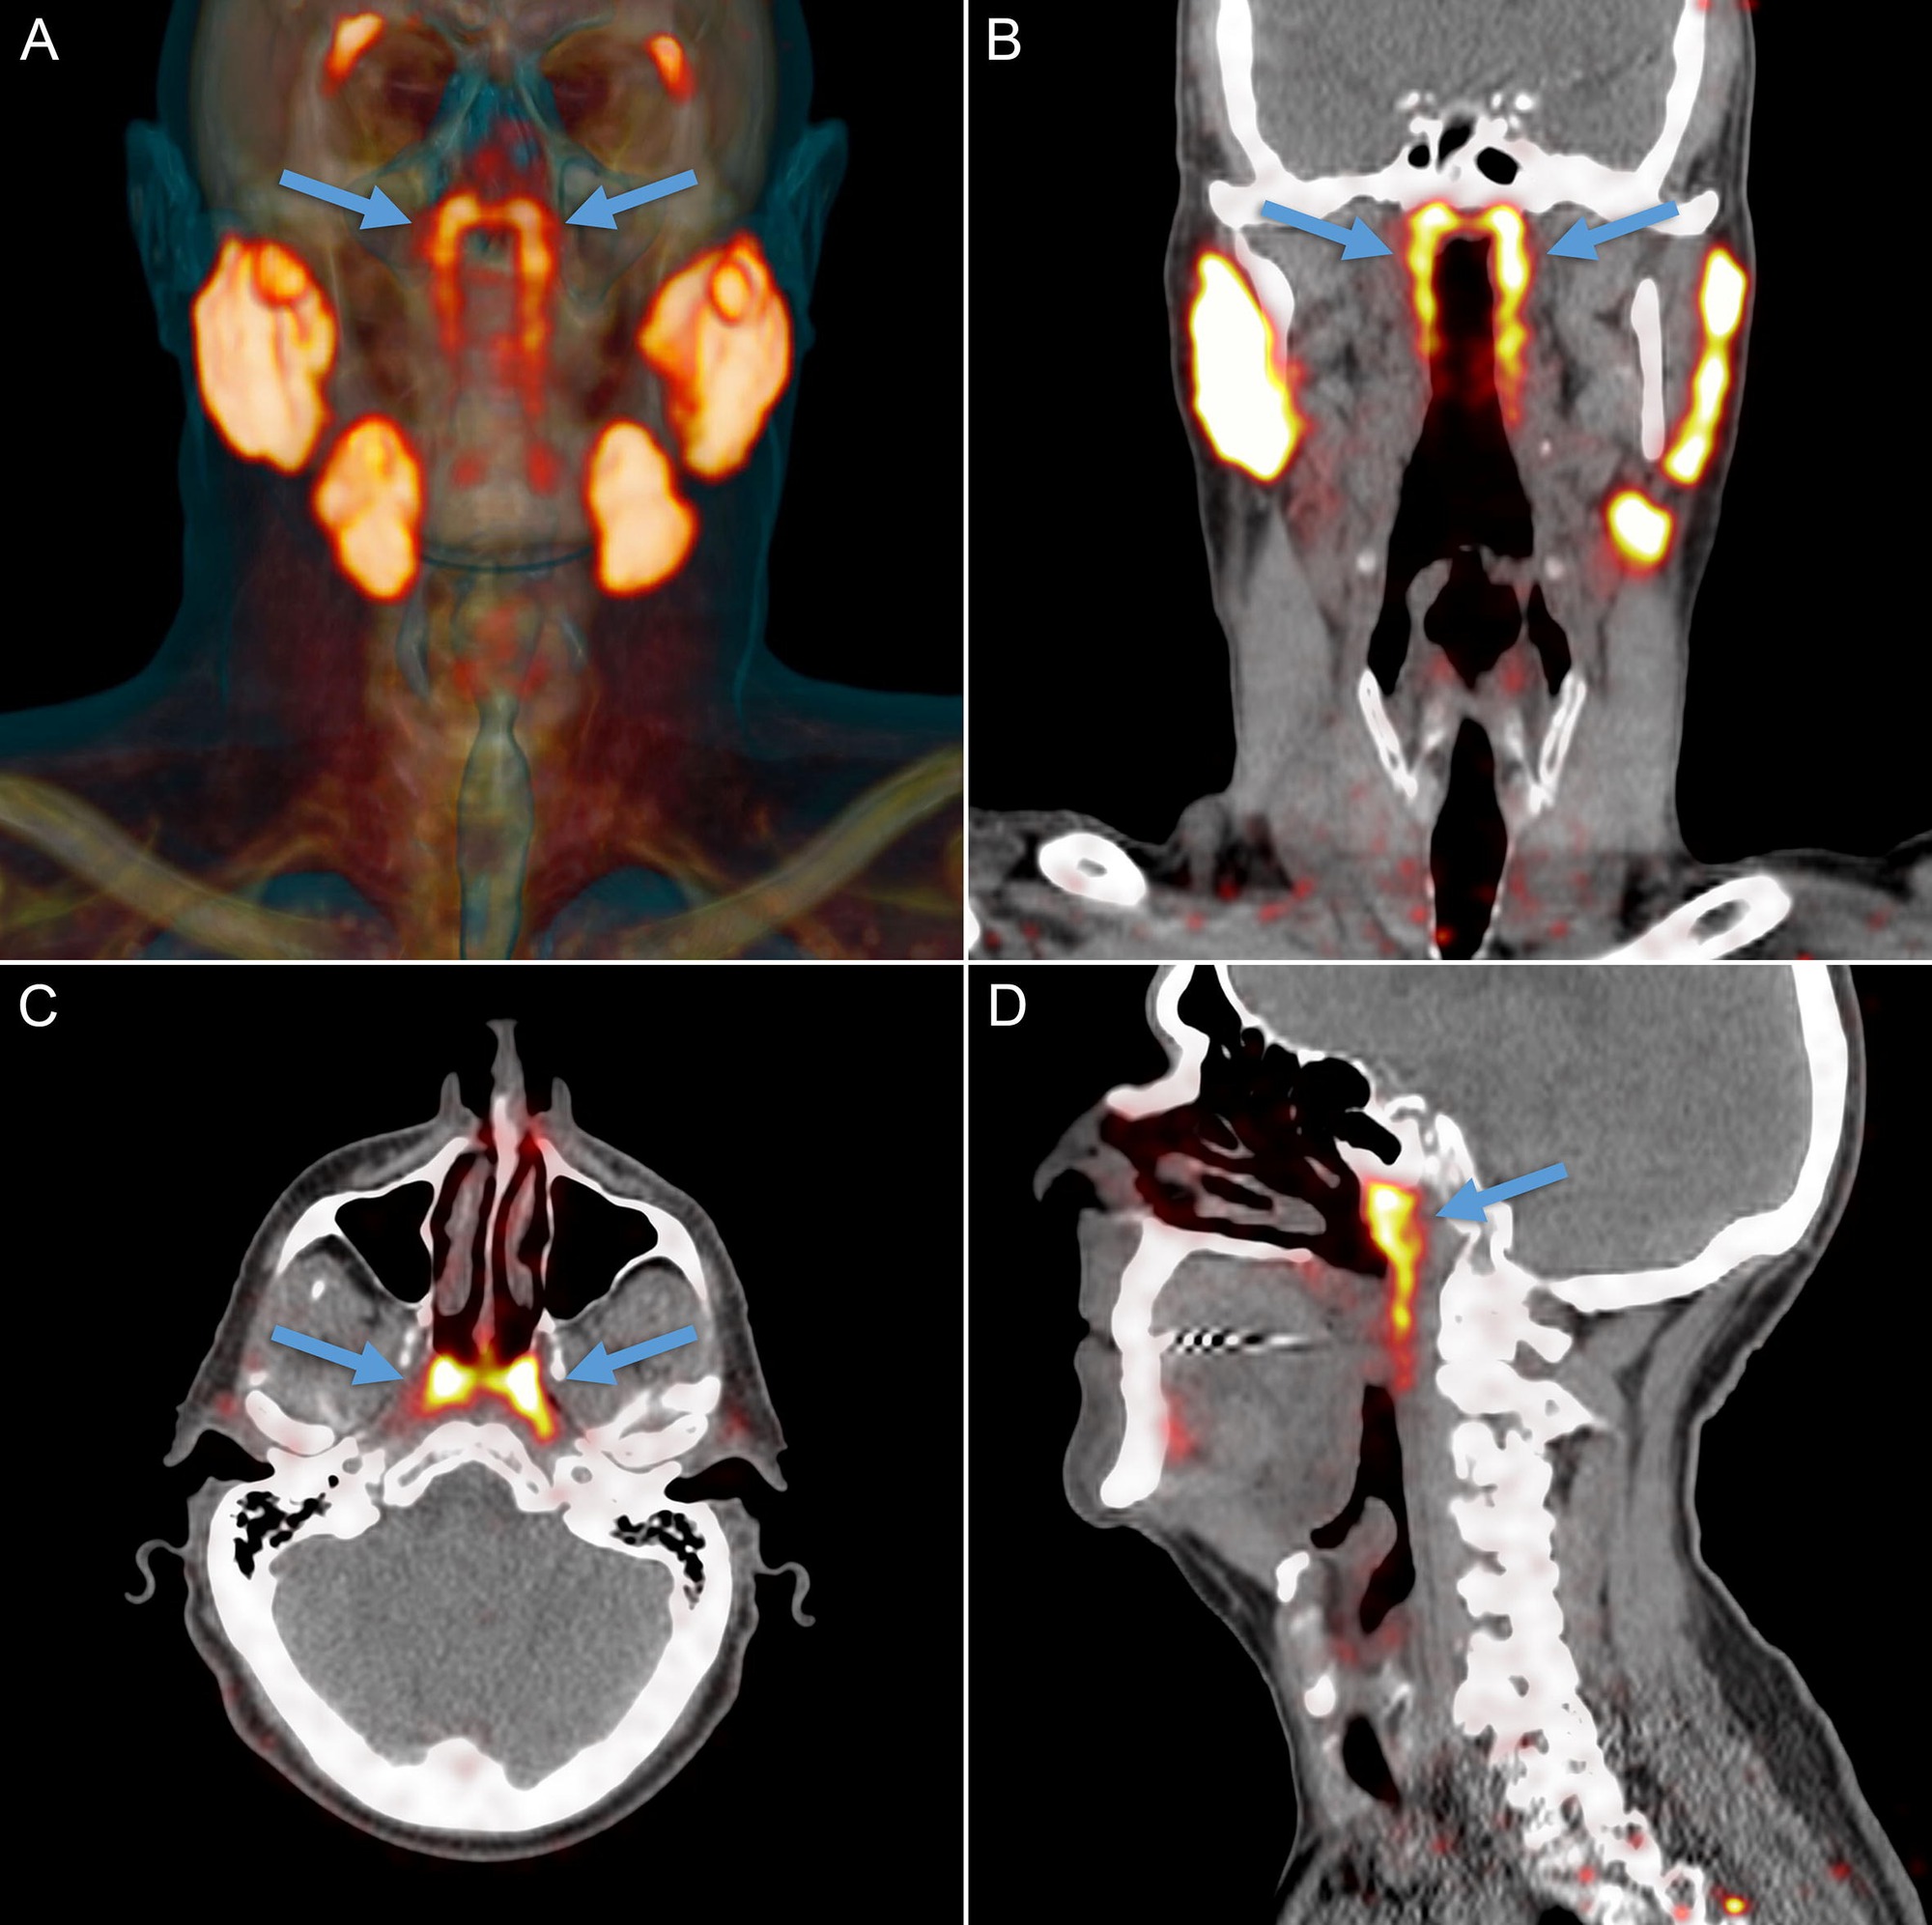

Một phát hiện tình cờ trong lúc nghiên cứu ung thư đã dẫn các chuyên gia tới một cơ quan mới bí ẩn nằm sâu trong cơ thể người.